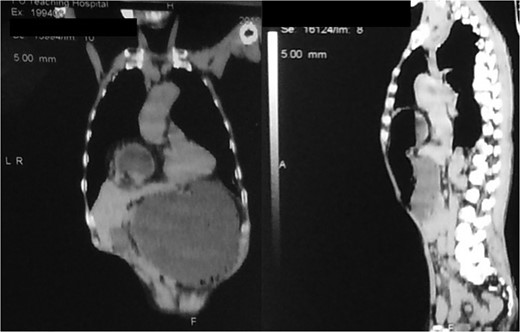

An 80-year-old man presented to our emergency room with multiple episodes of non-bilious vomiting for 4 days and not-passing stool or flatus for 2 days. He also complained of intermittent pain in the upper abdomen, which was not associated with fever, chest pain, melena or diarrhea in the recent past. However, he complained of increased cough and shortness of breath for the last 4 days on the background of a diagnosed chronic obstructive pulmonary disease. There were no similar complaints in the past. On examination, his vital parameters were normal, other than an oxygen saturation of 82% for which oxygen had to be given via face mask. His abdominal examination revealed epigastric fullness with tenderness in the epigastric and right hypochondrium. There was no evidence of peritonitis. Laboratory investigations revealed hypokalemia (3.1 mEq/l) with other parameters being normal. On the chest X-ray obtained, we saw air–fluid levels in the right thoracic cavity (Fig. 1). Computed tomography (CT) scan of the abdomen performed demonstrated a right anterior diaphragmatic hernia with stomach as content. (Figs 2 and 3) The patient was taken to the operating room, and an upper midline laparotomy was performed. Findings included an ~4 × 3 cm defect to the right of the sternum in the anterior diaphragm (Fig. 4), with incarcerated pylorus/antrum of stomach as contents and a grossly distended stomach. Rest of the bowel was normal. The contents were reduced, and the defect closed primarily with 2-0 non-absorbable interrupted mattress sutures (Fig. 5). Postoperative period was uneventful, and chest X-ray revealed a corrected defect with reduced contents (Fig. 6). The patient was started orally on the first postoperative day and discharged on the sixth postoperative day.

Diagnosis is usually suggested by chest X-rays indicating an air–fluid level in the chest with Barium studies revealing contrast in the stomach/bowel herniating through the diaphragm. CT scan of the chest and diaphragm are highly accurate and help proceed with surgical management [7].